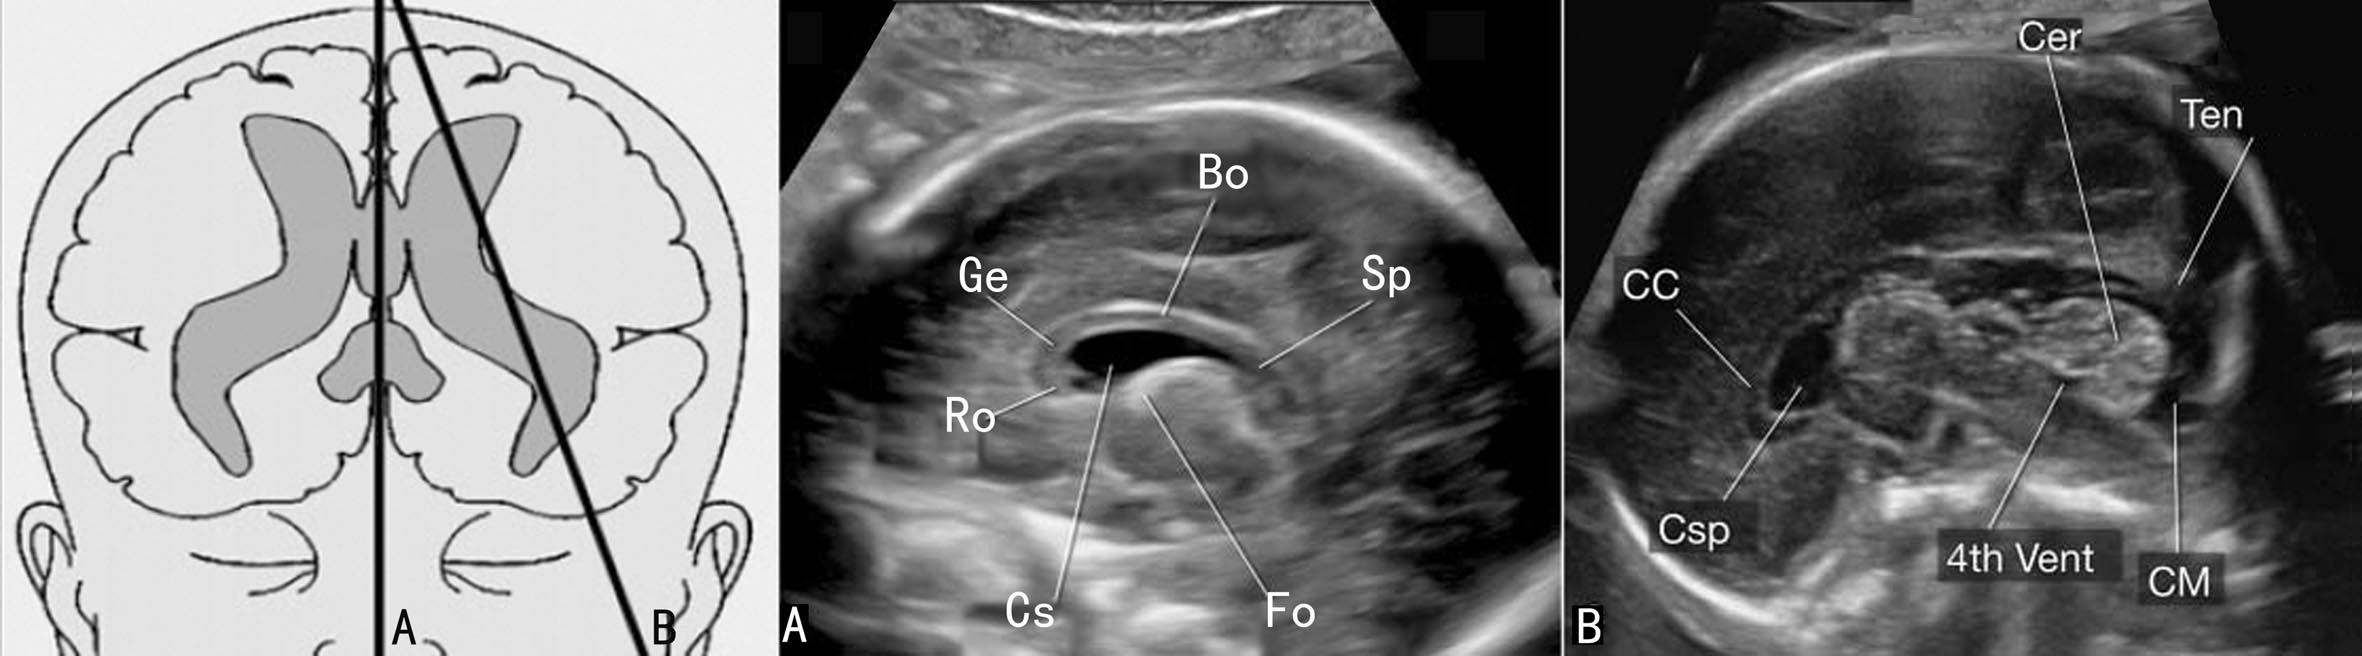

图7-1胎头横断面声像图

1.TVP 颅骨显示为环状椭园形强回声,回声对称。切面中显示的逗点状无回声为侧脑室(TV)前角和后角,后角内稍强回声的脉络丛(CP)近充满TV,形态规则,边缘清晰;中线回声的前部的无回声为透明隔腔(CSP),在妊娠晚期(TTP)或新生儿期CSP消失形成透明隔(SP)。PUE中CSP显示非常重要。一般在妊娠18~37周都可显示SP,<18周或>37周时可能不显示。CSP的显示与否有助于鉴别一些脑部畸形。

TVP还可显示中部两侧部分丘脑,脑中线可见。TV额角内侧壁几乎和大脑镰相平行,枕角向两侧分开离脑中线较远(图7-1A)。测量枕角与额角内径可判断有无脑室扩张,整个妊娠期间TV枕角内径均<10mm。STP由于CP呈强回声致其远侧大脑皮质回声低或极低,应注意和TV扩张或脑积水区别。

2. TTP 在TVP向下水平移动探头即可获得TTP,此平面是测量BPD的标准平面。颅骨呈椭圆形环状回声,对称,脑中线居中,中线回声的前1/3处的等号样回声为SP,SP之间的腔隙为CSP,正常时内径<10mm。由前向后可显示TV前角、对称的丘脑和海马回(图7-1B),小脑不显示;两侧丘脑之间的缝隙为第三脑室,正常时<2mm,向前经室间孔通向TV,向后经中脑导水管通向第四脑室。

3. TCP 获得TTP后声束略向尾侧旋转,即可获TCP。标准切面要求同时显示左右对称的小脑半球以及前方的CSP(图7-1C)。SP前外侧仍可显示TV前角,小脑与SP之间中线两侧的低回声为丘脑;小脑呈对称的半球形或蝶形回声,实质部分回声较低,随着妊娠的进展内部回声逐渐增强,但边缘回声增强更为明显;晚孕期小脑实质近边缘区域显示数条整齐的线状强回声为小脑裂。正常发育的小脑与孕龄有良好的关系。两侧小脑之间有回声较强、不均匀的小脑蚓部,后方与小脑相邻的无回声为小脑延髓池(CM)(图7-1C)。20孕周以前CM没有完全覆盖第四脑室,或可引起小脑或小脑蚓部畸形的假象,应当于20孕周以后予以确认。